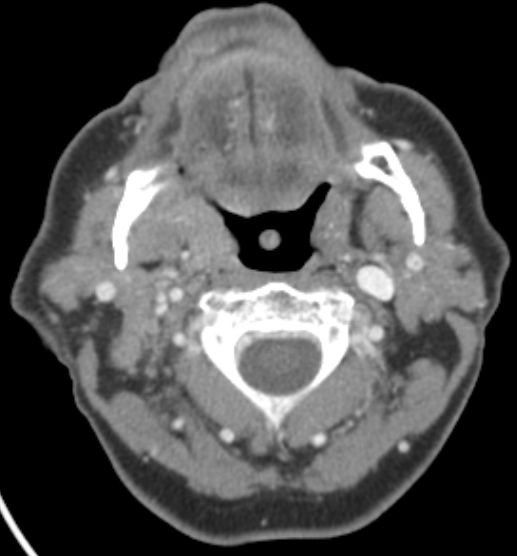

| CT | Alveolarkamm - Karzinom des linken Unterkiefers mit großem Lymphknotenkonglomerat unter dem Musculus sternocleidomastoideus

![]() |